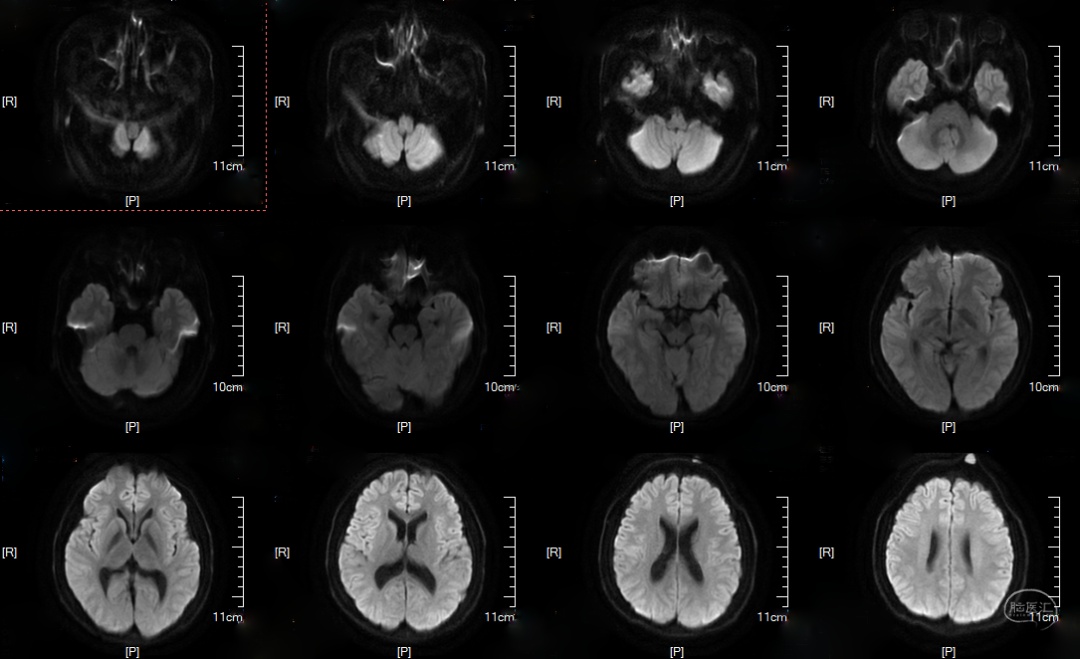

DWI: